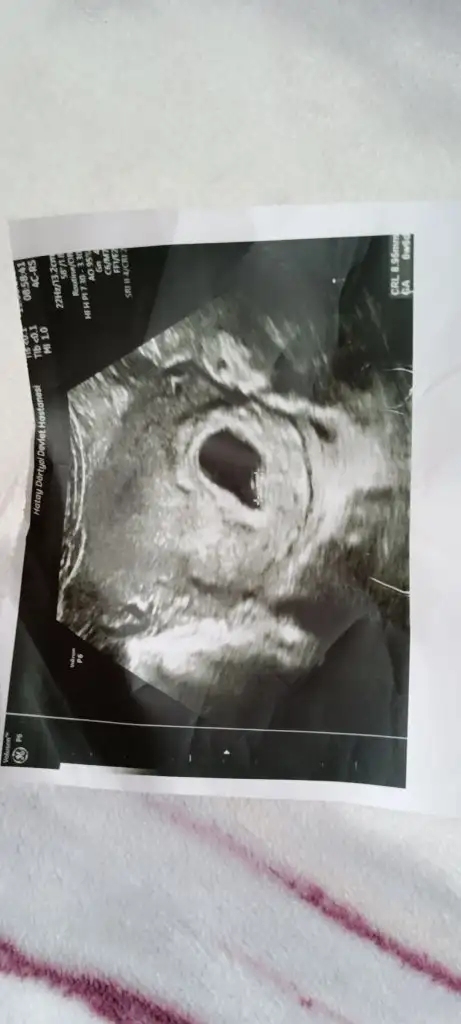

8 haftalık karından .Bana da tahminde bulunur musunuz 😊